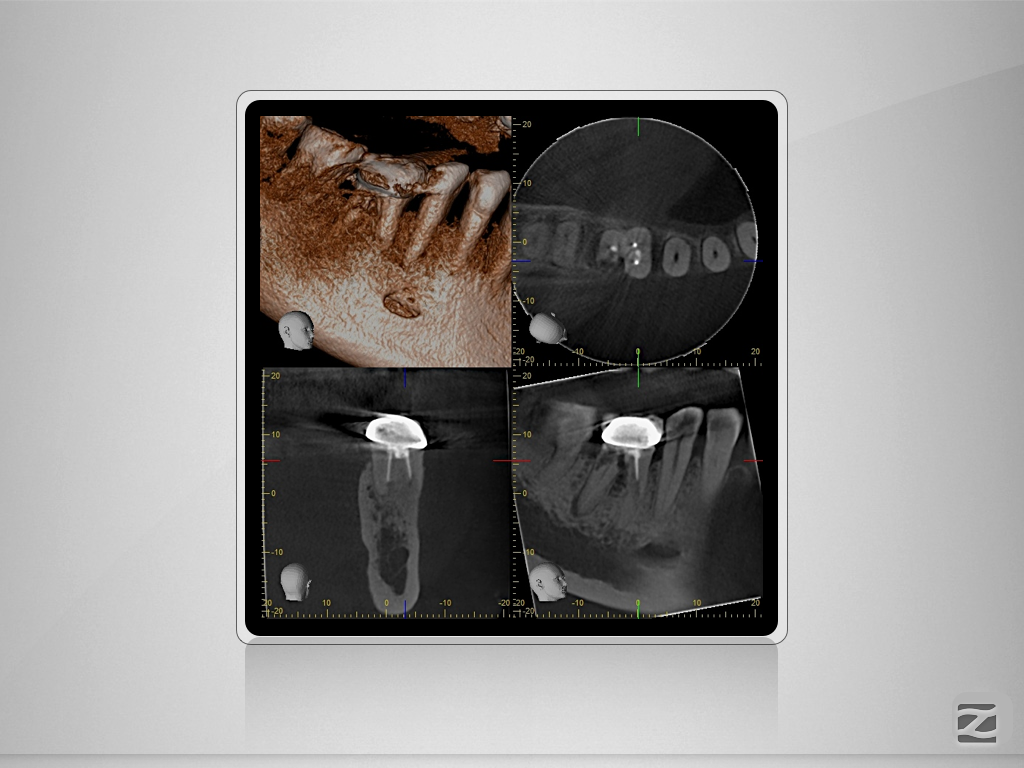

46D.006

2D vs. 3D (XXVIV)